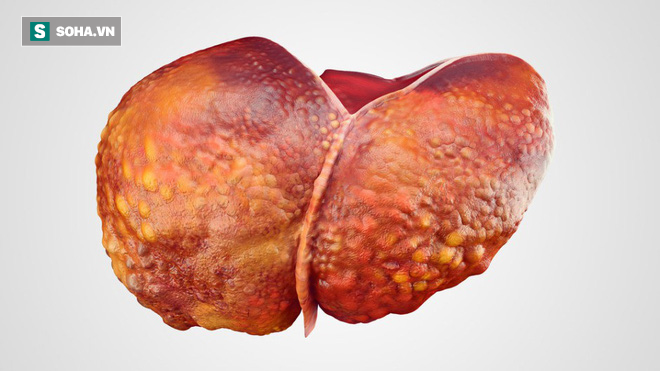

2. Người đang bị xơ gan

Bước tiếp theo trong diễn tiến của nhóm người bệnh xơ gan thường là ung thư gan, đặc biệt là ở những bệnh nhân đã được các bác sĩ phát hiện xơ gan. Cần phải điều trị tích cực và hiệu quả hơn.